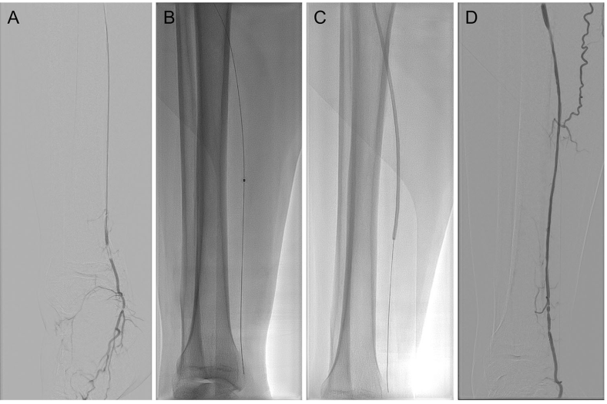

★手术过程

术中顺行穿刺到达狭窄或闭塞病变段附近,在病变段近端予硝酸甘油/罂粟碱扩血管及尿激酶溶栓,导丝通过狭窄或闭塞病变段到达远端流出道后,在膝下动脉使用准分子激光系统(CVX-300 准分子激光系统)减容。采用0.9mm-2.0mmELCA激光导管,以小于 0.5-1 毫米/秒的速度缓慢通过病变段,激光能量30-60mJ/mm2,频率25-80Hz,重复2-3次。在获得管腔后,使用1.5mm-3.0 mm球囊进行球囊扩张。

当ELCA导管无法通过闭塞病变段时,将尝试使用1.5 mm球囊预扩张。当激光导管和球囊均未能通过动脉时,认为激光辅助球囊扩张治疗失败,仅予扩血管、溶栓缓解下肢缺血后结束手术。

图:激光辅助血管成形术干预的DSA和IVUS成像。

(A) 基线血管造影; (B) 准分子激光减容; (C) 球囊扩张; (D)术后血管造影